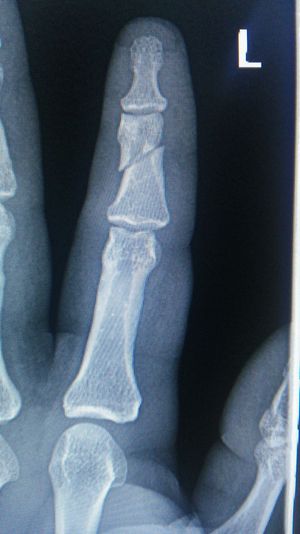

Xray

Fracture

Anularis